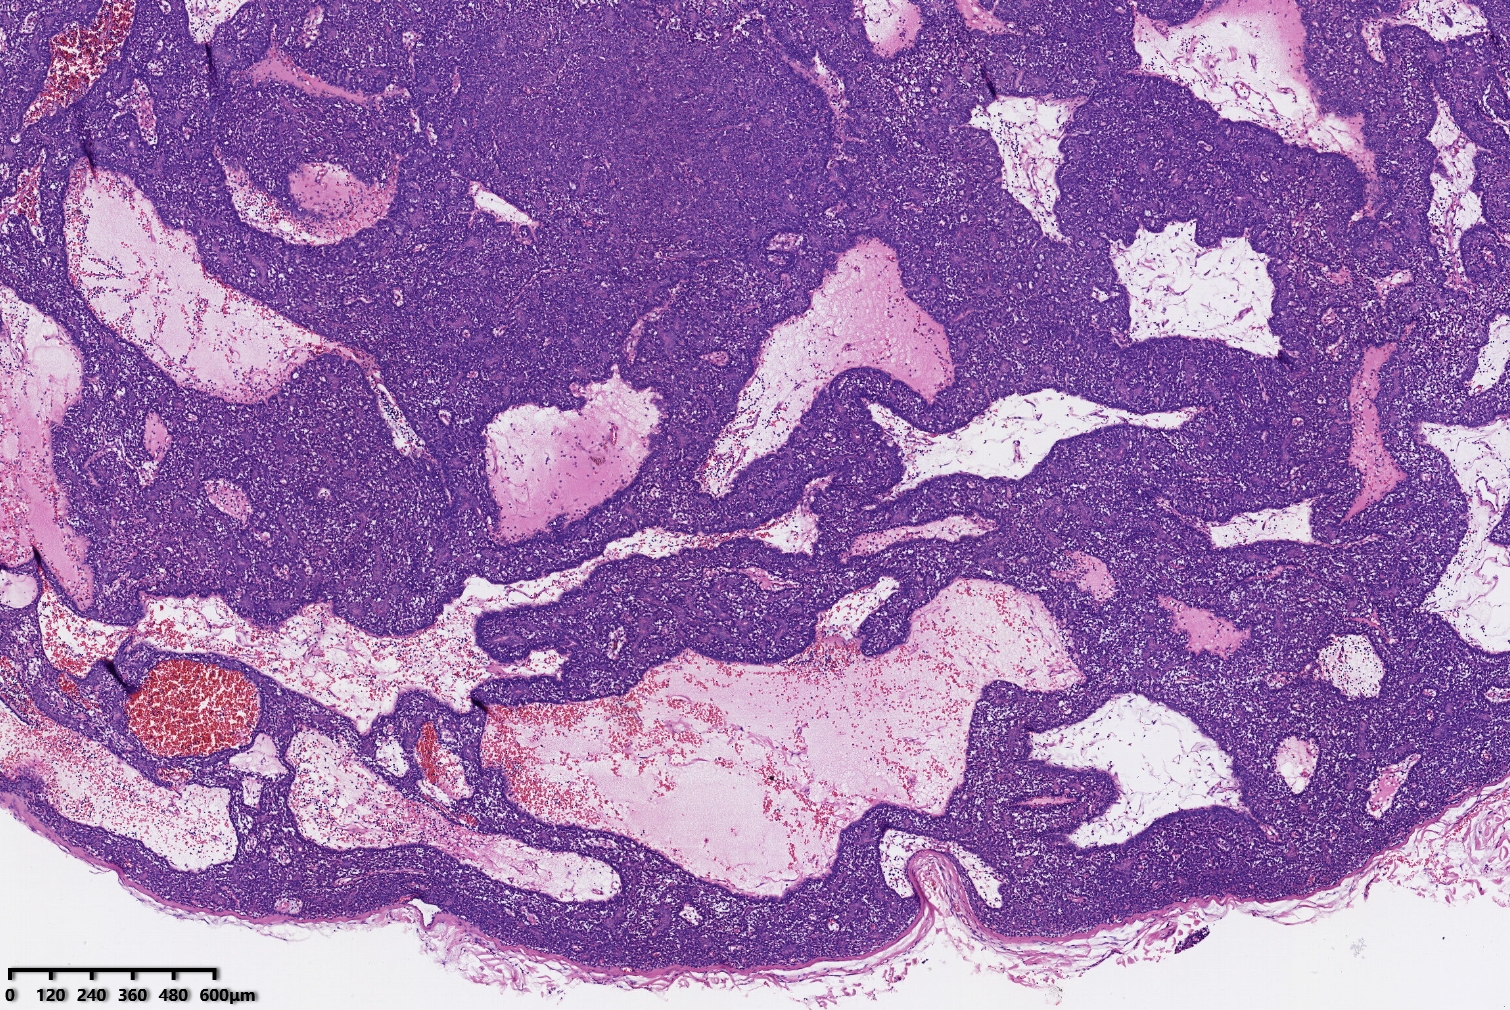

汗腺腺瘤?

背部包块

同意,有的区域像透明细胞汗腺瘤

小汗腺螺旋腺瘤